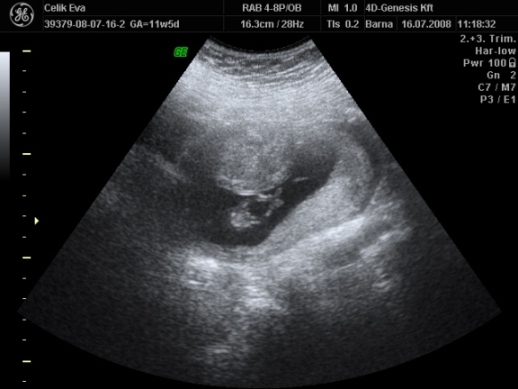

2d-s

ezen olyan aranyos baba arca van :lol: Kép

Kép Kép Kép

asiye

és a fütyi:

mindegyik deréktól lefelé van, a hasikájának a fele látszik, a lábacskákés közte a fütyi

az első kettő majdnem egyforma

a harmadik is deréktól lefelé de oldal irányból, itt talán jobban látszik a feneke alatt a fütyi mérete :lol:

érdemes a tappancsokat is megnézni :lol: